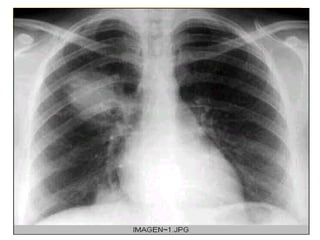

Bronconeumonía   Se produce una intensa inflamación en las vías aéreas y el parénquima pulmonar contiguo Opacidades en parches de contornos poco definidos que ocupan mas de un lóbulo   todo un pulmón o de forma bilateral   Puede estar presente el broncograma aéreo   Puede originarse con diversos organismos, aunque el más habitual son las bacterias. Es fácil que se origine después de haber sufrido un resfriado

Grupos que mas afecta:  los niños, los ancianos  , pacientes crónicos de diversas enfermedades como el asma, la diabetes o las cardiopatías  Bronconeumonía  curso mas agresivo que neumonia lobar Los sitios primarios de lesión son los bronquíolos terminales y respiratorios  con formación de úlceras e infiltración de sus paredes por   leucocitos   polimorfonucleares

engrosamiento peribronquial y tapones de moco  En contraste con la neumonía  lobar  que se caracteriza  por  atelectasia infrecuente, la bronconeumonía es una causa común de atelectasia  la  se ha denominado neumonía atelectásica .

Radiografía lateral de torax. Bronconeumonía con atelectasia.

Radiografía de torax, que muestra bronconeumonía en el pulmón derecho.